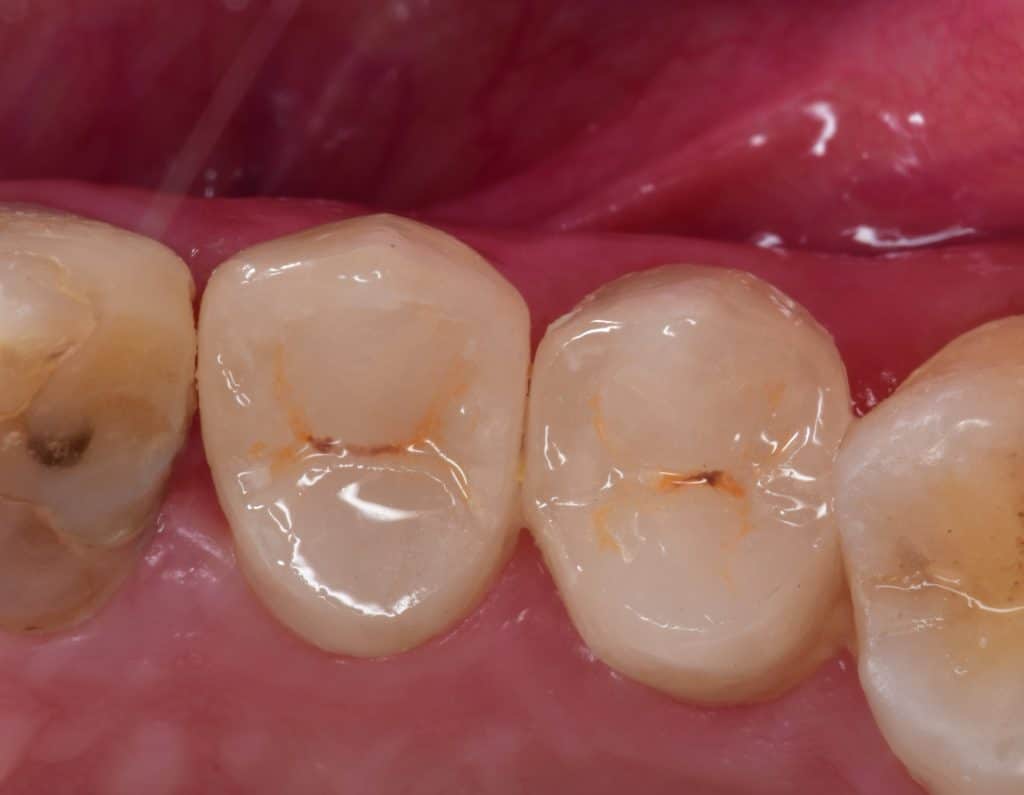

Initial situation showing large carious lesion in the upper premolars

Buccal view showing the extension of the caries